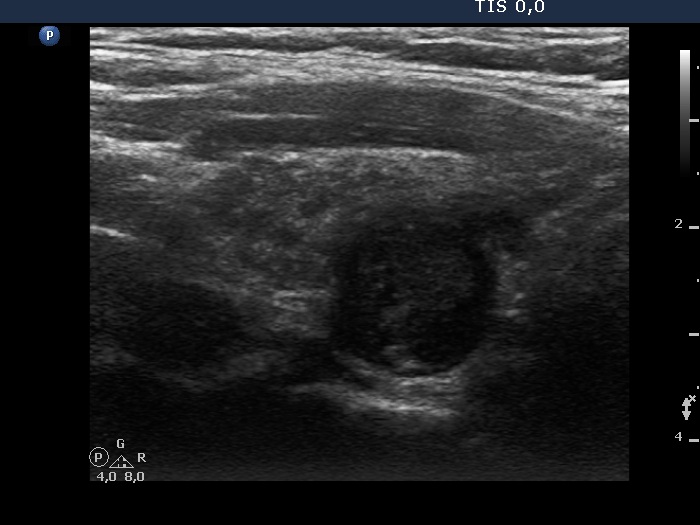

Second examination 2 years later (2nd row of images)

Clinical presentation. The patient had no complaints. The endocrinologist colleague noticed a significant increase in the size of the nodule on repeat ultrasound and he sent the patient for a repeat FNA.

Palpation: no abnormality.

Ultrasonography. The pattern was essentially the same. The only difference concerned the lesion in the dorsal part of the right lobe which clearly increased in size. Moreover, it became more obvious that the lesion had microcalcifications.

Aspiration cytology of the lesion resulted in Hashimoto's thyroiditis.

Suggestion: In agreement with the referring physician, surgery was proposed because there was a suspicion of thyroid cancer despite the negative cytology.

Histopathology disclosed Warthin-like variant of papillary cancer. and Hashimoto's thyroiditis.